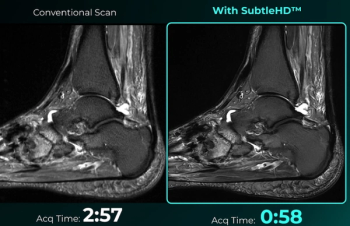

Enabling up to 80 percent faster MRI scan times, the SubtleHD software is included in the newly launched AI software suite Subtle-Elite.